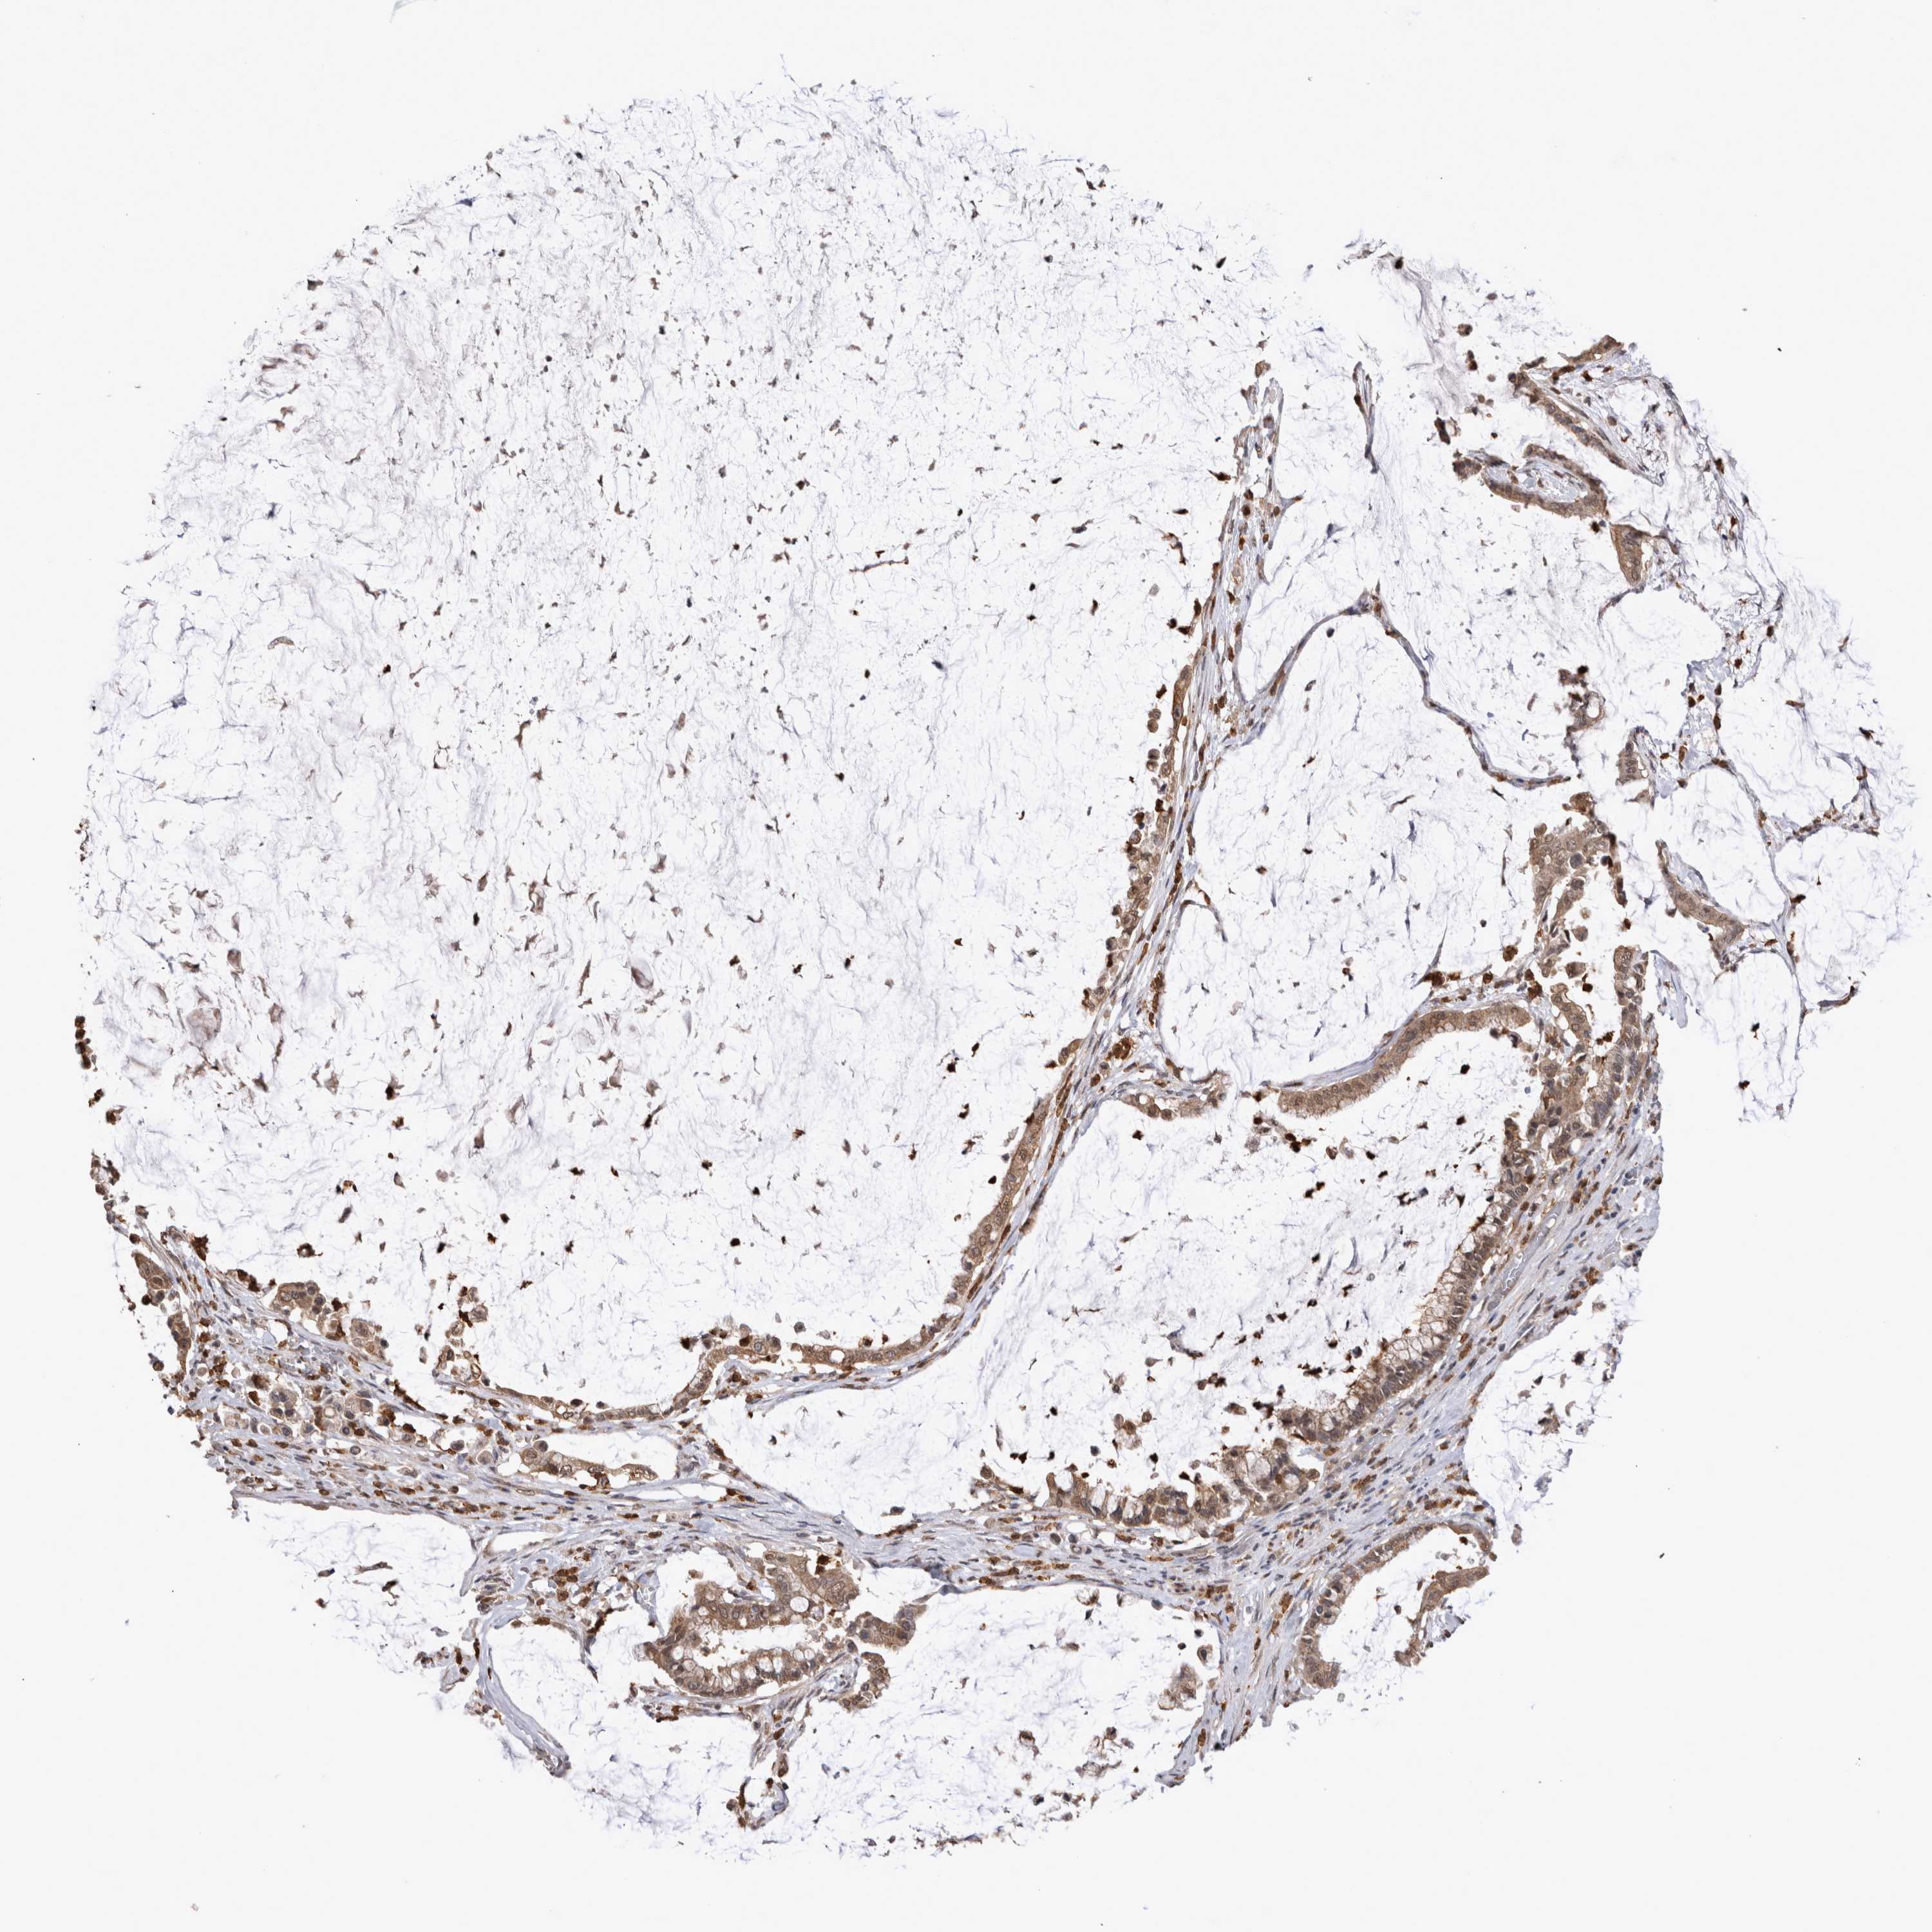

PANCREATIC CANCER - Protein expressioni

A mouse-over function shows sample information and annotation data. Click on an image to view it in a full screen mode. Samples can be filtered based on level of antibody staining by selecting one or several of the following categories: high, medium, low and not detected. The assay and annotation is described here.

Note that samples used for immunohistochemistry by the Human Protein Atlas do not correspond to samples in the TCGA dataset.

Antibody stainingi

Antibody staining in the annotated cell types in the current human tissue is reported as not detected, low, medium, or high, based on conventional immunohistochemistry profiling in selected tissues. This score is based on the combination of the staining intensity and fraction of stained cells.

Each image is clickable and will lead to virtual microscopy that enables deeper exploration of all samples and also displays staining intensity scores, fraction scores and subcellular localization as well as patient and tissue information for each sample.

Antibody CAB025747

Antibody CAB044670

Staining

High

Medium

Low

Not detected

Intensity

Strong

Moderate

Weak

Negative

Quantity

>75%

75%-25%

<25%

None

Location

Nuclear

Cytoplasmic/membranous

Cytoplasmic/membranous,nuclear

Adenocarcinoma, NOS

Adenocarcinoma, metastatic, NOS